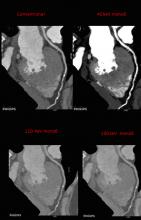

Computed tomography has seen rapid growth in all segments of medicine over the past two decades, and recent advances may further expand use of cardiac computed tomography angiography (CCTA). Advocates for cardiac CT speaking at the 2015 meetings of the American College of Cardiology (ACC), Society of Cardiovascular Computed Tomography (SCCT) and Transcatheter Cardiovascular  Therapeutics (TCT) laid out the latest technological advancements and outlined new clinical trial data that may help CT become a first-line, one-stop-shop cardiac imaging modality in the near future.